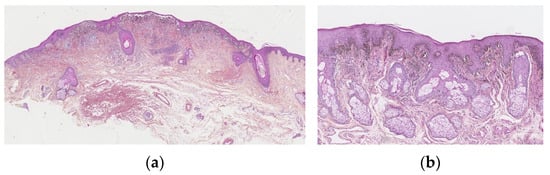

The junctional component is usually florid. They commonly show a mixture of several patterns. Most are in a nested pattern, where larger but variably sized, oval nests are predominant and can be oriented perpendicular and parallel to the dermo-epidermal junction. The dyshesive pattern shows discohesive nests, which may be almost contiguous, forming a band that separates the dermis from the epidermis. A crowded pattern is rarely seen with ill-defined nests and single melanocytes, which obscure the dermo-epidermal junction. The cellular nests may show prominent retraction artefacts. They can be irregularly distributed along the epidermal rete ridges, but sometimes confluent, with a parallel alignment to the dermo-epidermal junction. A huge lentiginous component can be seen. Pagetoid spread into the granular cell may be observed, but only focally and in the centre of the lesion. Adnexal involvement is frequent (Figure 2a,b).

Figure 2.

Atypical genital nevus. (a) Florid junctional component. Nests that show prominent retraction artifacts, are confluent, dyscohesive. Dense derman component with fibrosis. (b) Lentiginous epidermal component, bulky, epithelioid polygonal melanocytes with scant cytoplasm and angulated hyperchromatic nuclei, or multinucleated.

In summary, melanocytic atypia of the junctional component is typically present. In contrast to dysplastic naevi, melanocyte atypia is uniform, rather than random. Melanocytes may be epithelioid (without any other criteria of Spitz lesions), polygonal with scant cytoplasm and angulated hyperchromatic nuclei, or multinucleated. Infrequently, they have a spindle cell morphology. The epidermis may be acanthotic or atrophic.

The dermal component is often prominent and mushroom-shaped. It may display the same cytologic atypia seen in the epidermis, but there is no deep dermal or atypical mitosis, and there is a cytologic “maturation” visible. Broad bands of fibrosis may be visible in the superficial dermis. Some authors have suggested that all these lesions need excision, and this is often performed in adults. However, in children, where there is no change and there are normal dermoscopic features, follow-up with clinical photographs and dermoscopy is a very reasonable approach [15].

Melanocytic proliferations with LS are rare and are histologically difficult to interpret [18]. They have features in common with persistent nevi, also called recurrent nevi or pseudomelanomas, that are recurrences of pigmentation that appear after incomplete removal of a nevus and can mimic malignant melanoma [19,20]. They can also present with criteria that are those of atypical naevi (Figure 3a,b). Morrel compared 5 biopsies from naevi without LS and 12 with LS: cytological atypia was seen in 83% versus that seen in 40% without LS. The same author, from the Dutch Pathology Registry database, identified 16 cases of atypical naevi in the context of LS, coming to the conclusion that 36% of all nevi with LS are atypical, versus 4.6% of all vulval naevi in young people.

Figure 3.

(a) Junctional naevus in the context of lichen sclerosus: band-like superficial fibrosis, epidermis showing a tendancy to atrophy and ll-defined, irregularly pigmented lesion. (b) Lentiginous epidermal component, dyscohesive, confluent, ill-defined epidermal nests, melanophores in the superficial dermis.